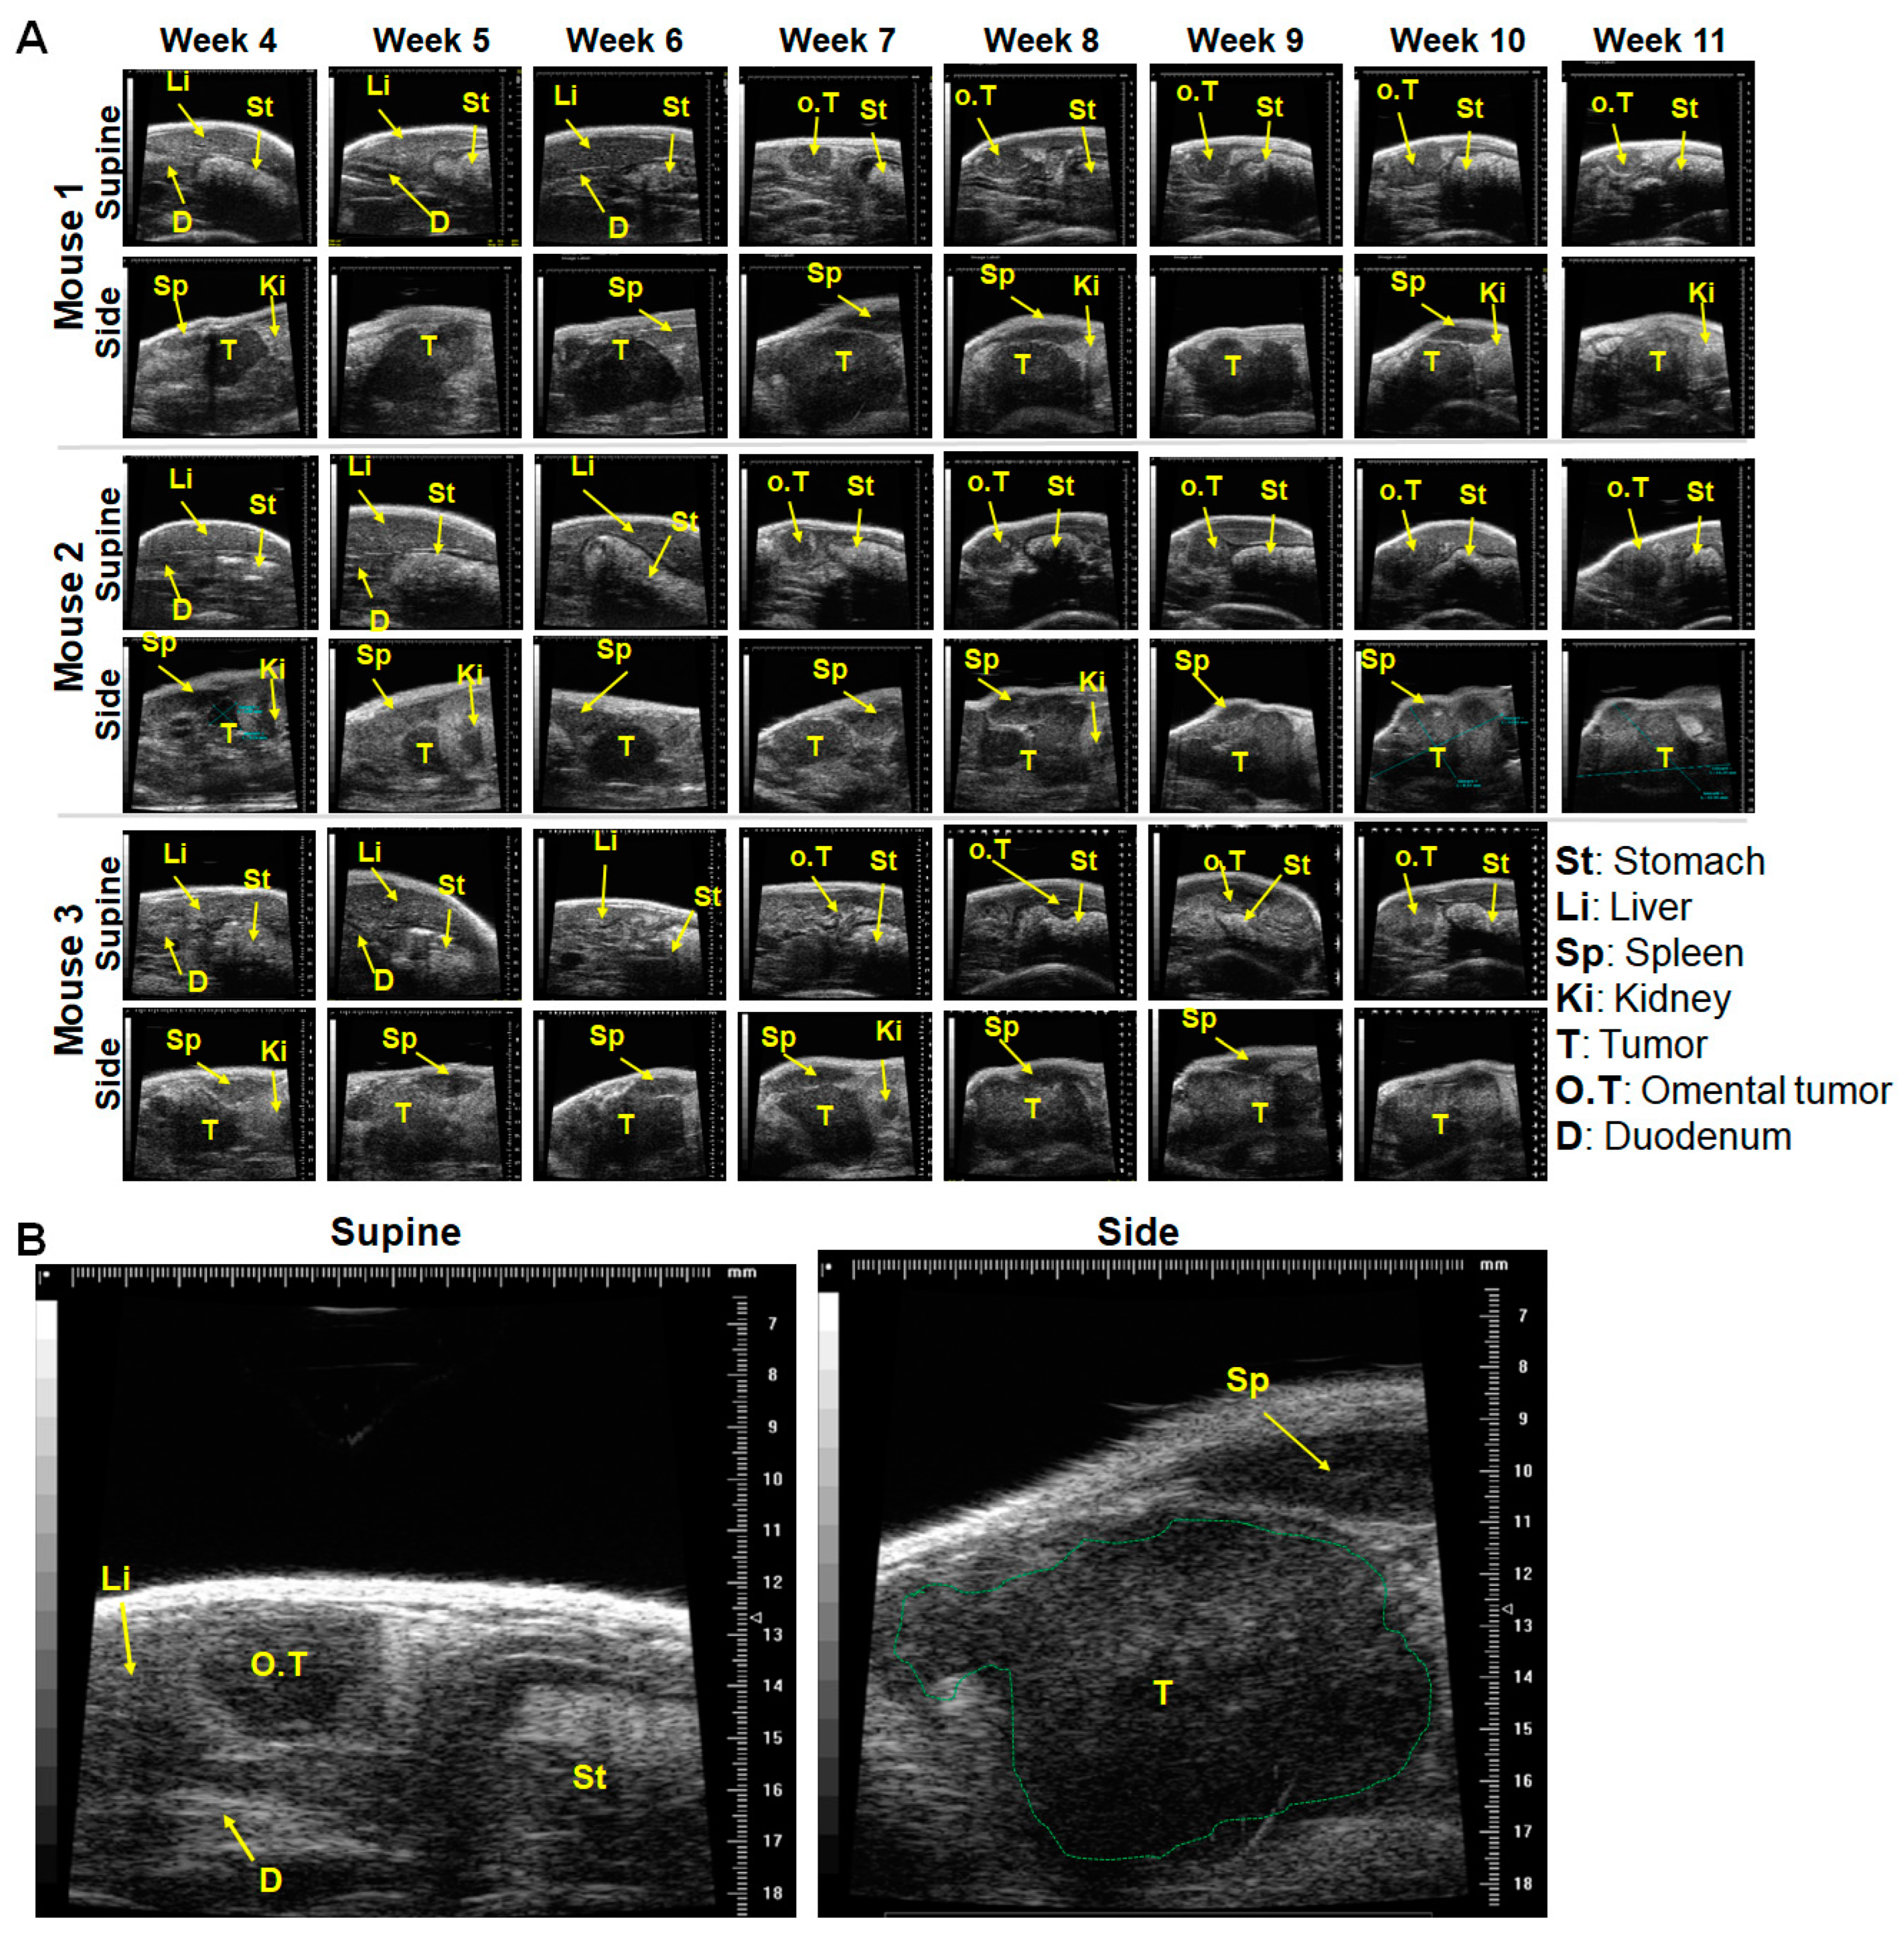

2.1. In a Minor Number of Mice, Implanted Tumors Remained Secluded within the Pancreas, and Almost Outgrew the Pancreas over Time

2.2. Tumor Infiltration of Vital Organs and Disease Progression

- Ultrasound imaging should be carried out preferentially both on the side and supine position in order to monitor the primary tumor and to pinpoint the onset of the infiltration of the omentum and/or stomach wall and metastasis. Furthermore, the use of imaging systems that have higher penetration and/or additionally provide functional and molecular information of the tumors [54] should be considered.

4.4. Monitoring the Orthotopic Pancreatic Tumor Growth by Ultrasound (US) Imaging